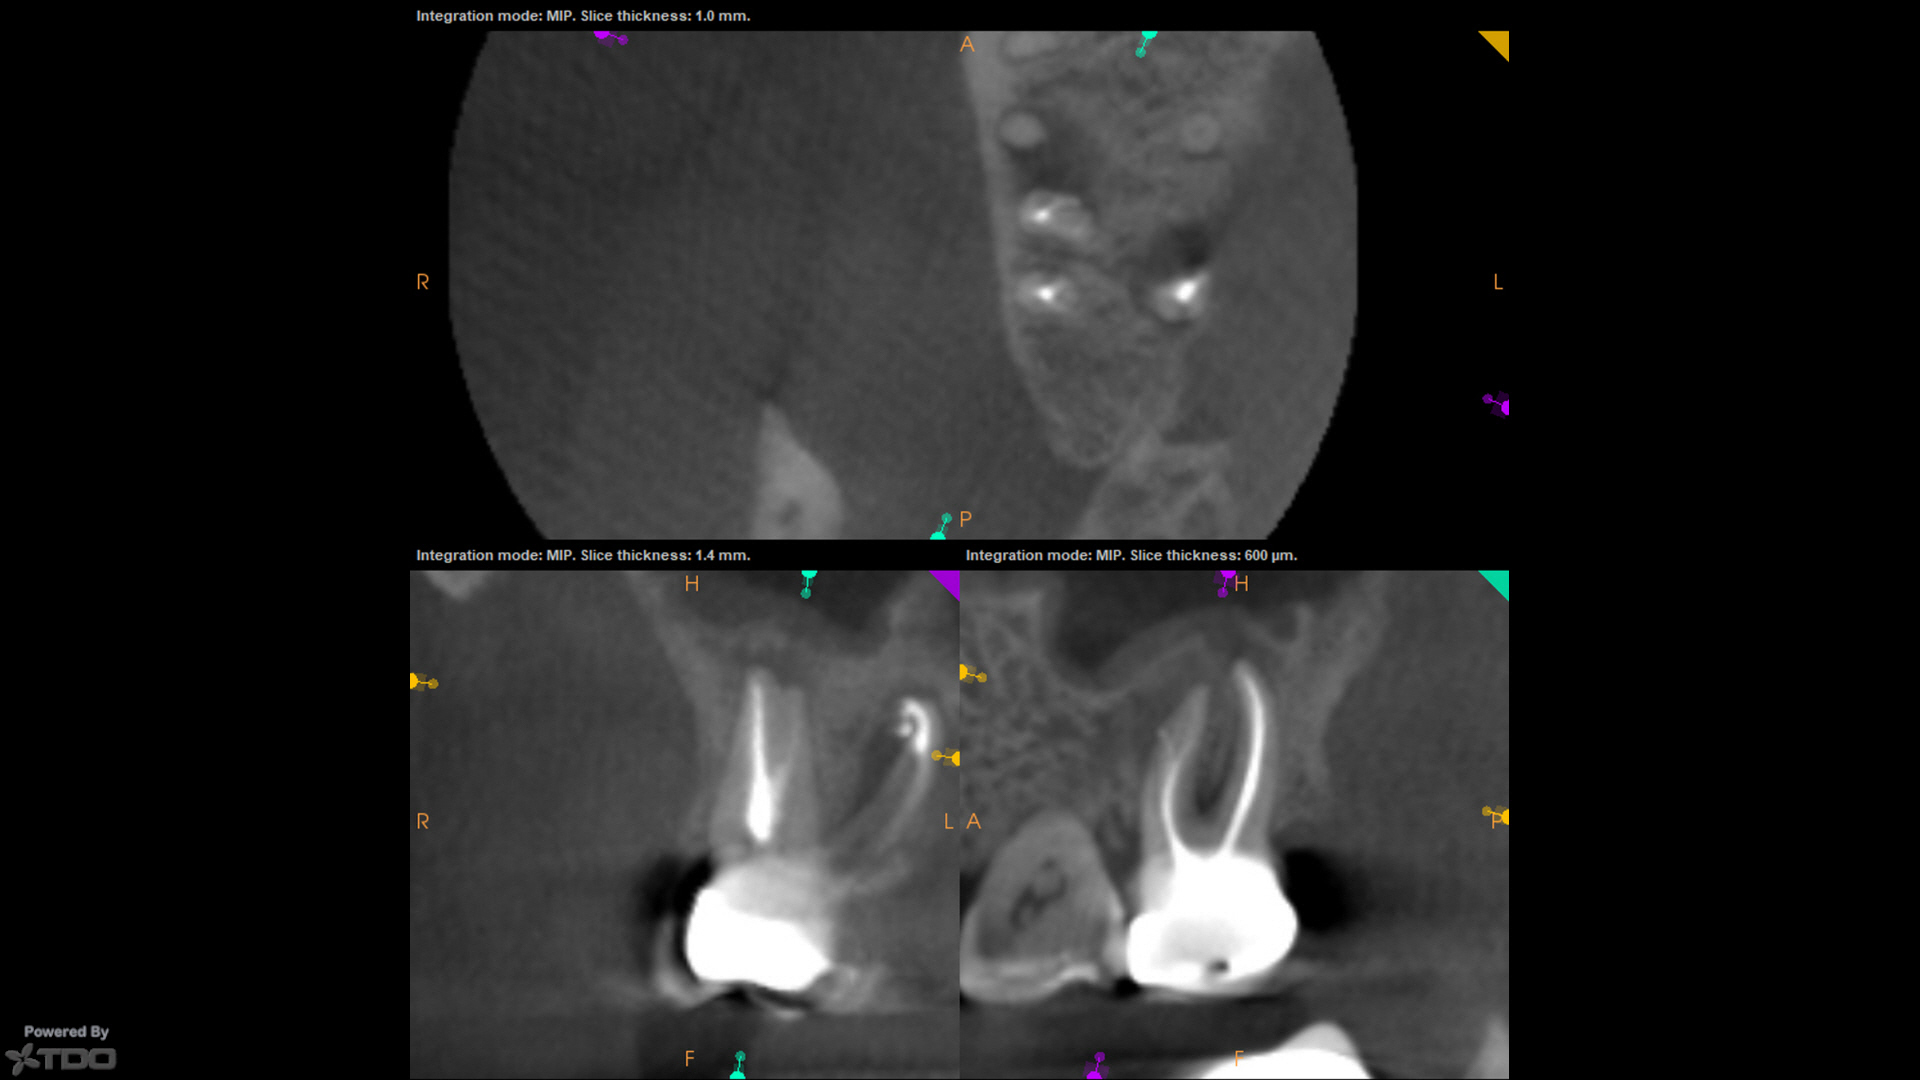

Process-outcomes were highly touted, many shown in setting sealer, some with CBCT, like this case from today (now yesterday), and then the inference made that those process-outcomes were a function of the GW.

As this now-asymptomatic case from today (now yesterday) shows, that also is not the case.

From the interim CBCT, I knew we had a deep split and separate MB2 POE.  I obturated the MB canal with BC Sealer and a single cone, making no effort to do anything with the MB2 from a "cleaning and shaping and obturation standpoint."  No downpack was performed.  CBCT demonstrates at least something in MB2, as well as a lateral canal off-to-the-mesial.  No GW was used.

I think claiming some sort of victory here is misleading at best, and attributing the process-outcome to some trick intervention parameter is…well…I'll wait for the followup…